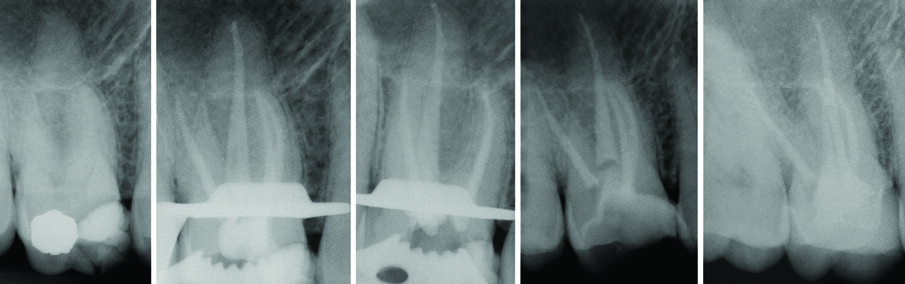

All’esame radiografico le otturazioni appaiono dense ed omogenee, la guttaperca mostra un buon adattamento alla morfologia endodontica, determinando un buon riempimento delle irregolarità del sistema canalare. Sono stati evidenziati la presenza di canali laterali ed uscite apicali multiple. Figg. 8a-8e molare superiore, Figg. 9a-9e molare inferiore, Figg. 10a-10c molare superiore, Figg. 11a-11d anatomie complesse premolare curvo e Figg. 12a-12d ottavo.

Figg. 5 - A, rx preoperatoria 3.5 cura incongrua, B dopo strumentazione prova cono ad 1 mm, C cono master diametro in punta 45 con cemento, D rx dopo aver condensato il cono master mediante spreader in NiTi, E rx dopo otturazione mediante guttaperca plasticizzata.

Fig. 8 - Terapia canalare 1.6 controllo a 17 anni.